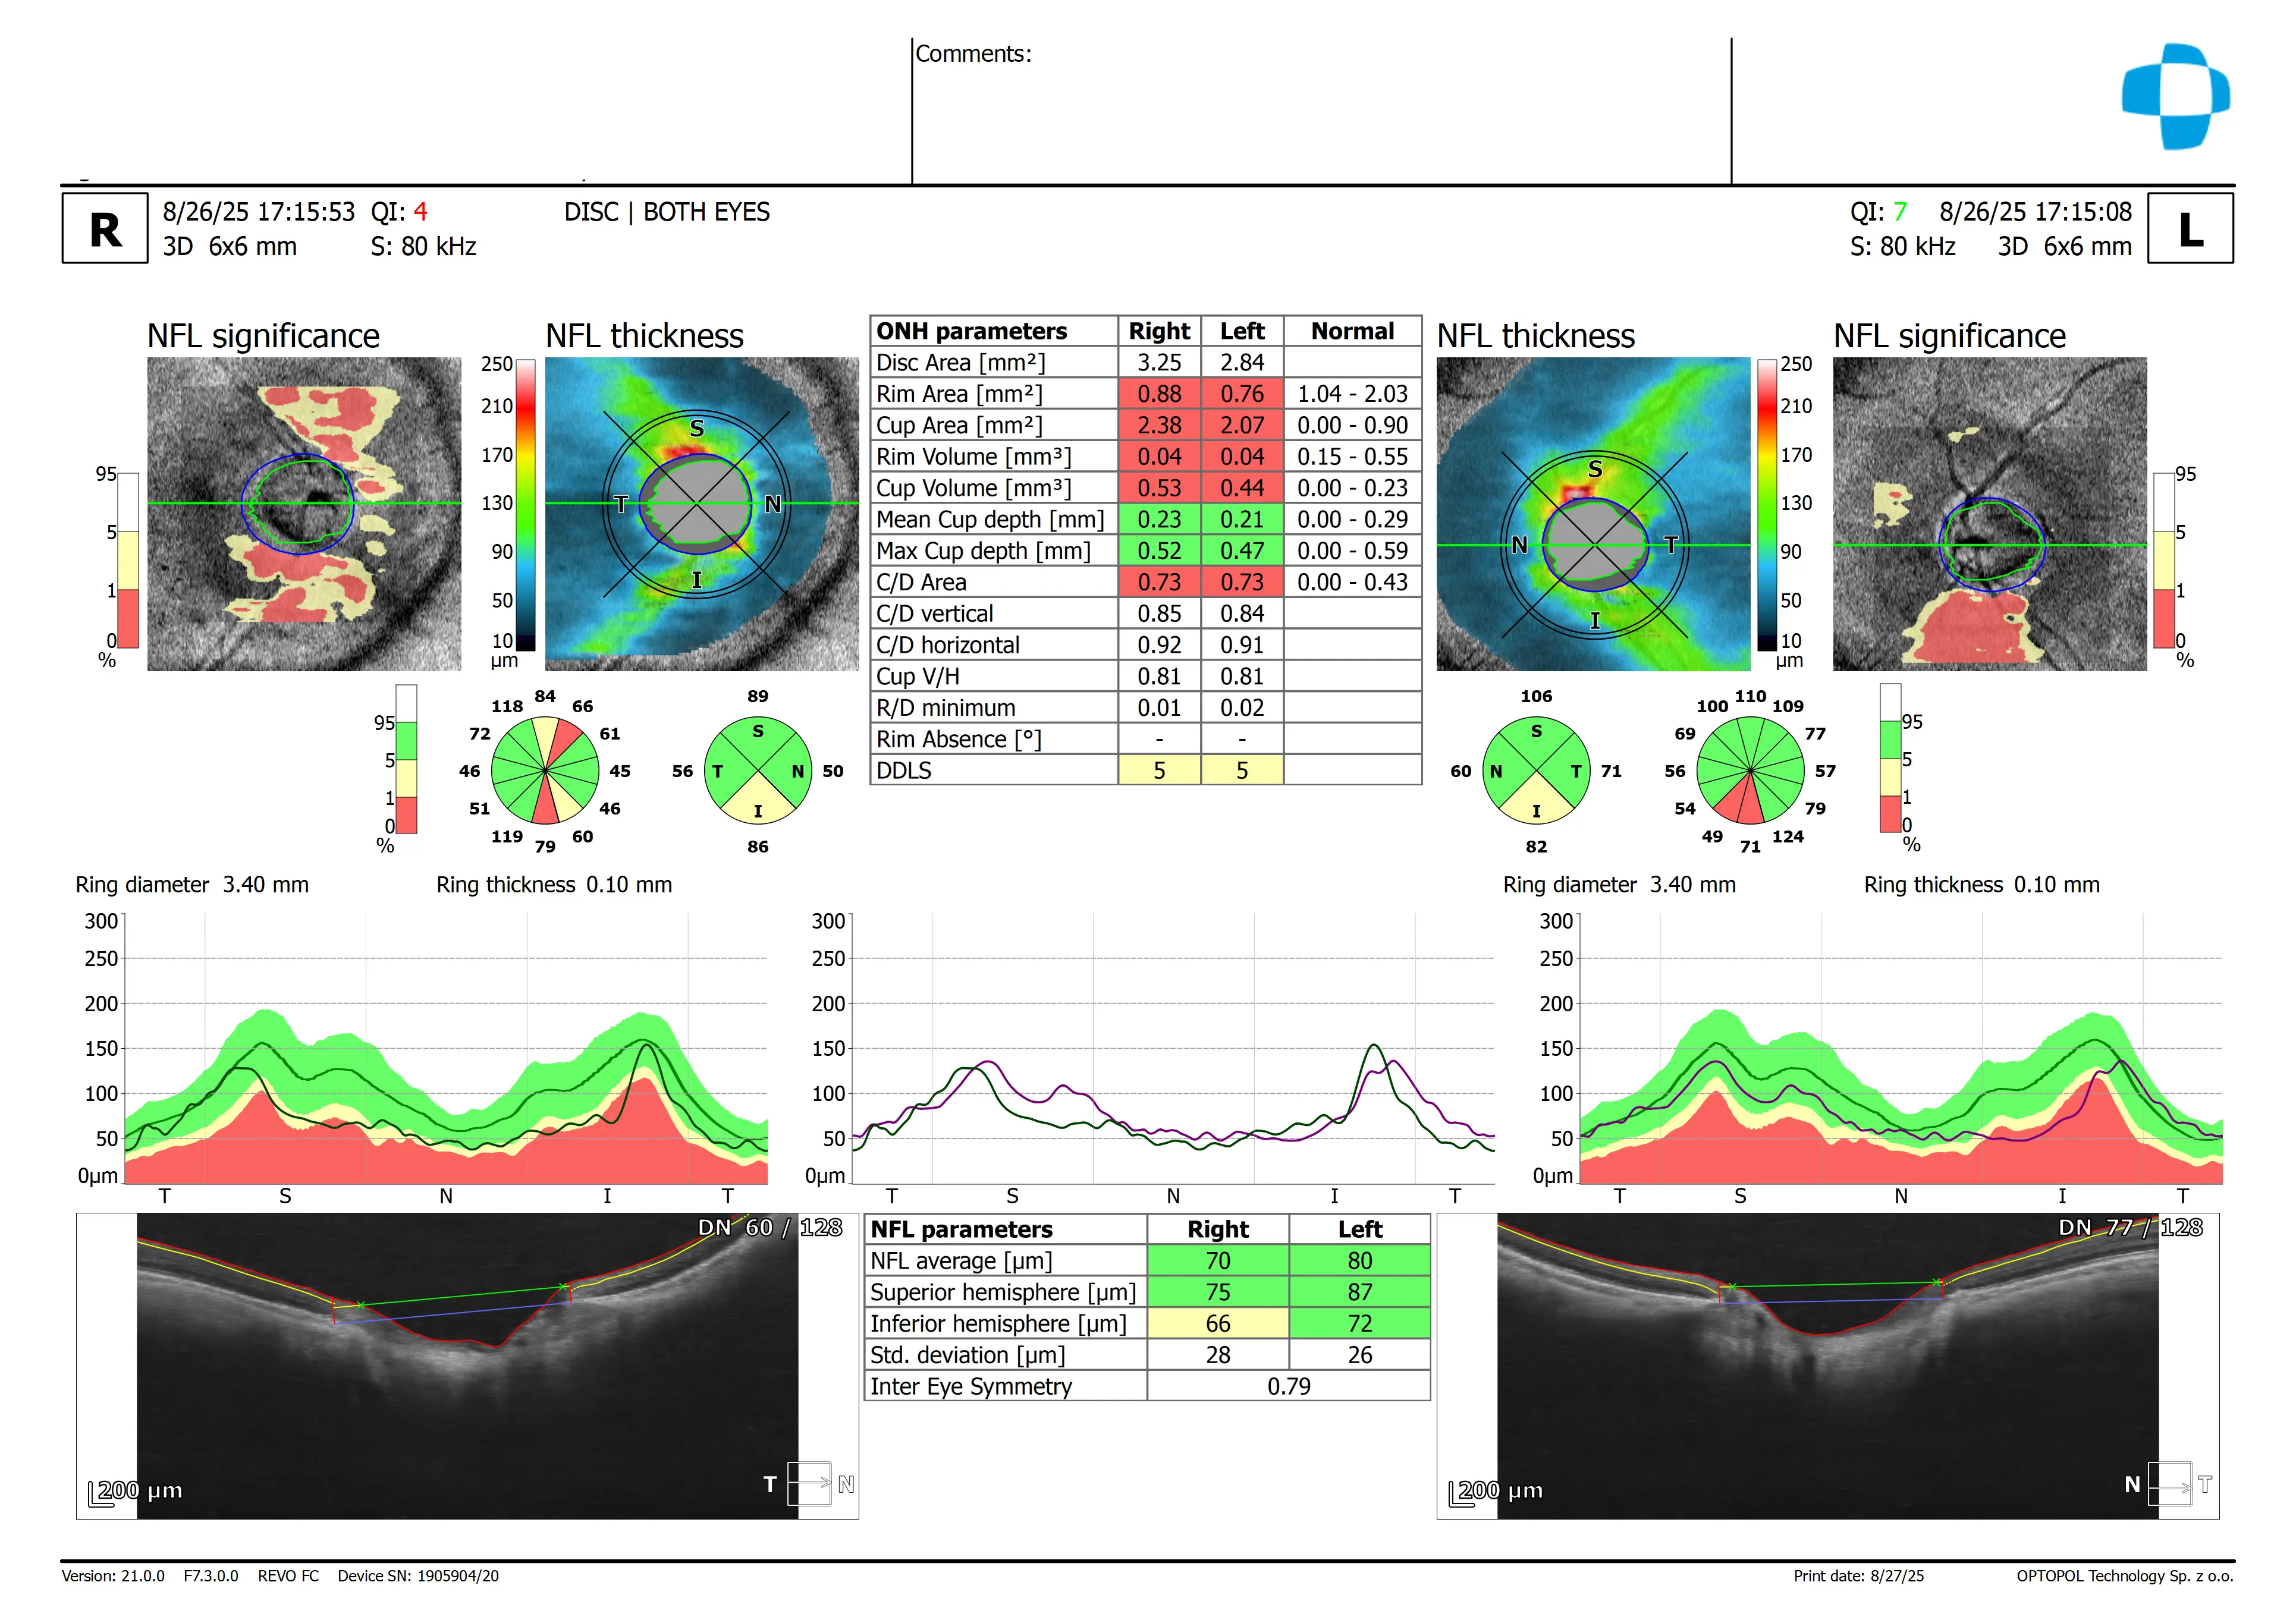

In-office examination showed best-corrected visual acuity of 20/20 in both eyes. Intraocular pressure was IOP OD 23 mmHg, OS 24 mmHg. Anterior segment examination revealed clear lids, lashes, conjunctiva, corneas, and deep quiet anterior chambers. Lens changes were minimal. Optic nerve evaluation demonstrated large discs with intact neural rims and myopic crescents, with mild inferior retinal nerve fiber layer thinning. Posterior segment evaluation showed a mild epiretinal membrane in the left eye.

OCT imaging revealed thinning of the retinal nerve fiber layer (RNFL) inferiorly in both eyes, without corresponding visual field defects.

Spectral-domain optical coherence tomography (SD-OCT) is a noninvasive imaging technology that provides high-resolution visualization of retinal and optic nerve head structures, including the retinal nerve fiber layer and ganglion cell layers. It allows for objective measurement and comparison to normative databases to detect structural changes. SD-OCT can track changes over time through repeatable scans, helping distinguish true anatomical loss from normal variation. Interpretation requires attention to factors like signal quality and individual anatomical differences.

Studies have shown that retinal nerve fiber layer (RNFL) thickness measurements obtained with spectral‑domain OCT (SD‑OCT), especially when analyzed by quadrant or clock‑hour sectors, can help distinguish glaucomatous eyes from normal eyes with high diagnostic accuracy.